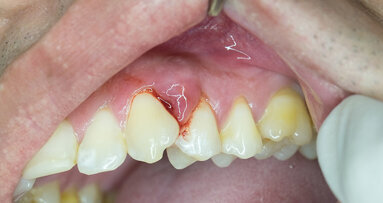

The scientists found two gene regions that appeared to be associated with an increased risk of developing different forms of periodontitis. One of the two regions is responsible for the synthesis of alpha-defensins (antimicrobial peptides), which are produced by specialised immune cells. These immune cells, neutrophils, are part of the body’s immune response and are involved in the identification and destruction of microorganisms. The second gene region inhibits the activation of these immune cells.

“Our results show that the different forms of gum disease share a common genetic origin,” said Schäfer. He emphasised: “This means that there are groups of patients who are susceptible to developing gum disease, but whose susceptibility is independent of other risk factors, such as smoking, oral hygiene or aging.”

Worldwide, the prevalence of severe periodontal disease is estimated to be about 11 per cent. The disease is considered complex because individual susceptibility is determined by the interaction between the oral microbiome and the immune system, smoking and diet, as well as by metabolic disorders such as diabetes mellitus. The response of the body to these factors is largely influenced by the individual’s genetic make-up.